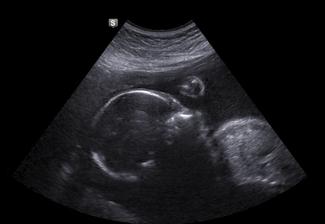

23tt + 1